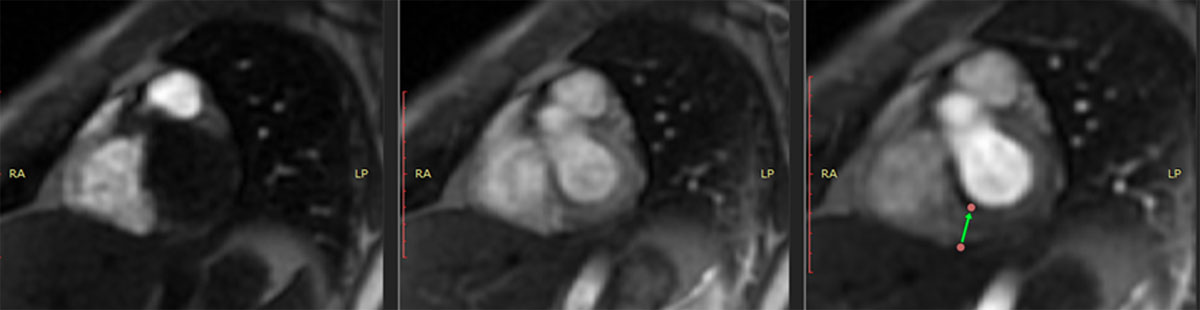

Figure 3

Cardiac MRI showing hyperemia in the basal portion.